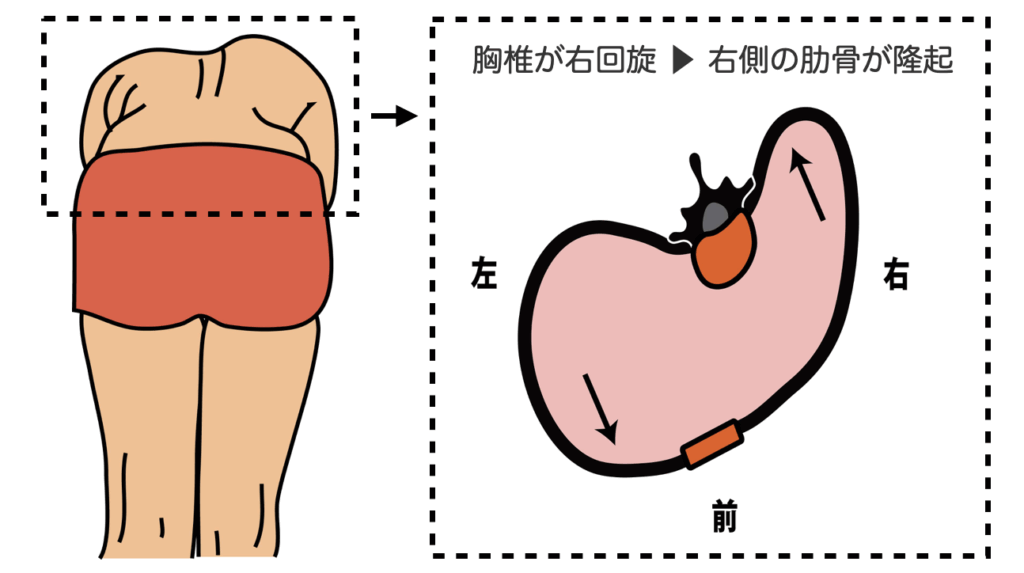

回旋:胸郭のリブハンプ(前屈で顕著)として現れる

前屈でのリブハンプ(胸郭の隆起)

リブハンプ:胸郭の隆起。前屈で目立つ。回旋変形の鏡。